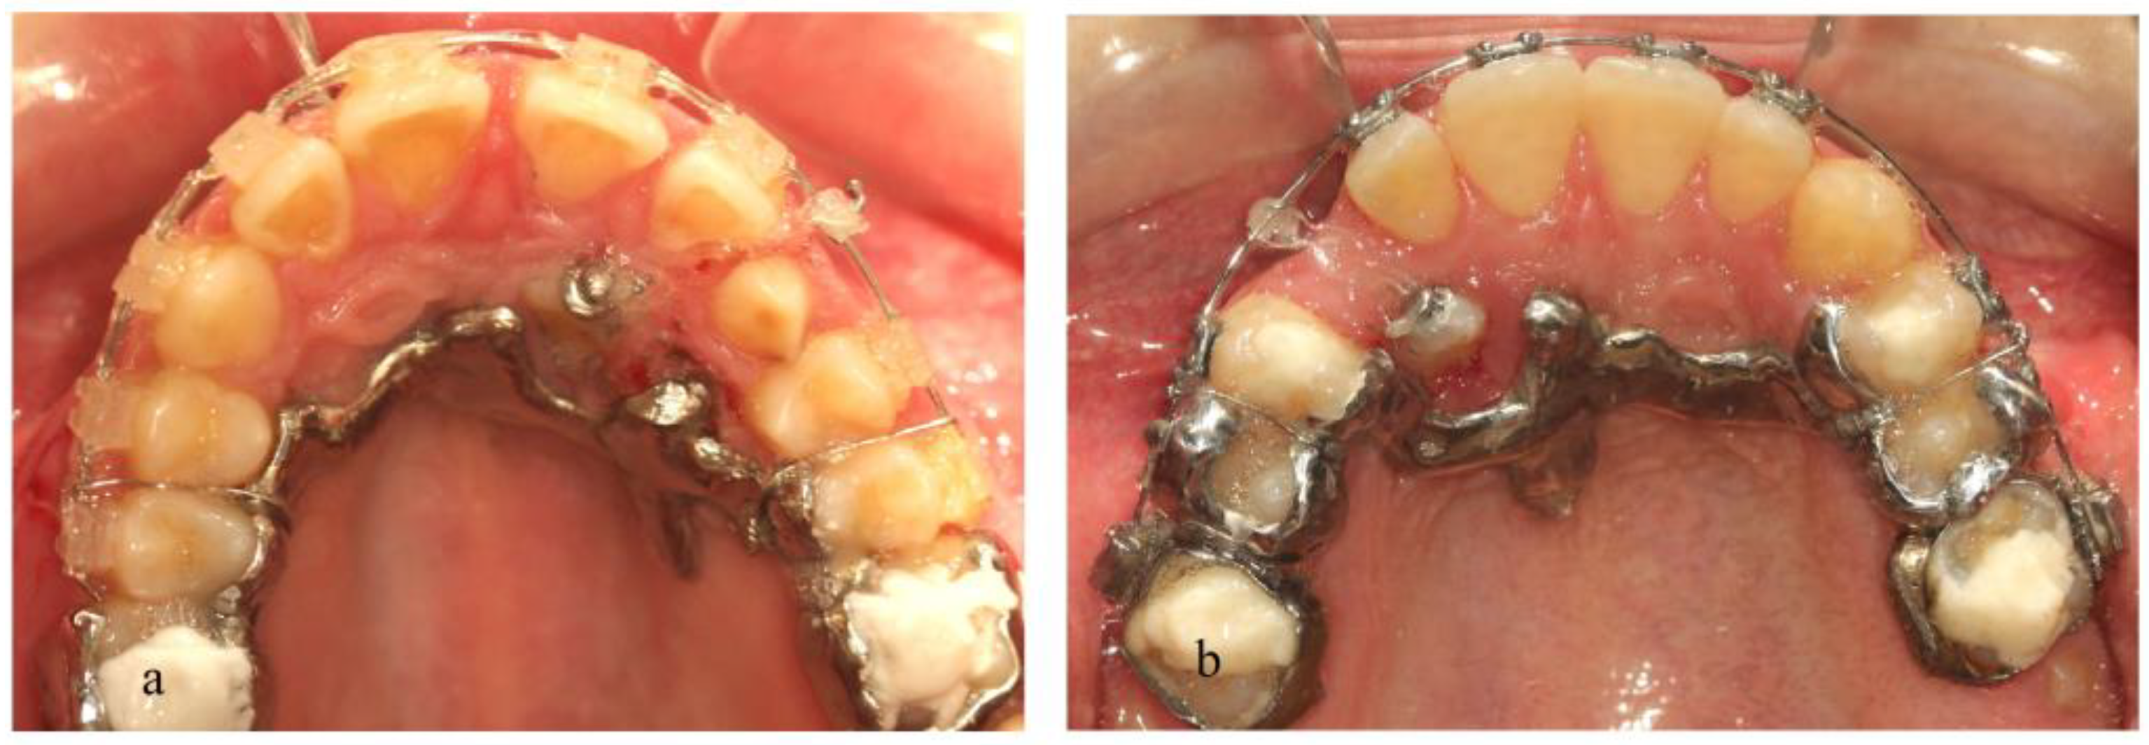

2. Materials and Methods

3. Results